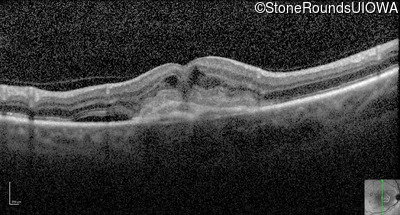

Optical Coherence Tomography - Left - 20/30

Exemplar / OCT Stack

Infrared Fundus Photograph - Left - 20/30

Exemplar